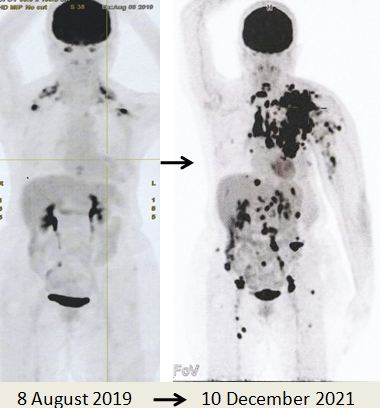

Due to the massive metastasis as shown in the PET scan done on 10 December 2021, Lucy had no choice but to proceed with chemotherapy. Indeed the cancer had spread extensively.

8. PET scan on 14 April 2022 showed good response indeed.

1. Amazing results of chemotherapy. Compare these three pictures –

Left: After surgery Lucy was on alternative therapy, refusing to undergo chemotherapy. The result was extensive metatastasis (middle). Right: Lucy has no choice but to go for chemotherapy. The outcome of 6 cycles of chemotherapy was just fantastic! In my 25 + years dealing with cancer patients, I have never seen such a great outcome of chemotherapy. Salute the oncologist! You rescued her!

In fact, the results were so unbelievable that one is tempted to ask if it is for real and not a fake? My answer is NO, detailed study of the PET scan results below are real! Study the images carefully – those before and after  chemotherapy.

The one lesson I learnt is that while chemotherapy had earned bad reputation there are times that chemo did help and can save your life. So let us be open minded. There is no one rule for treating cancer.